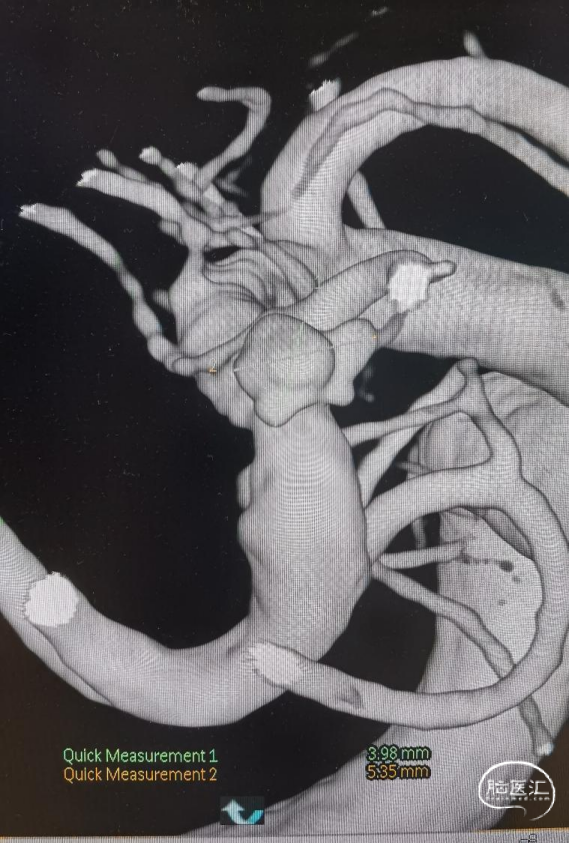

术前影像

CT显示广泛蛛网膜下腔出血,右侧侧裂池为著。

DSA示:右侧大脑中动脉分叉上干起始部宽颈动脉瘤,呈不规则分叶状,载瘤动脉管径纤细,角度锐利,载瘤动脉直径1.45mm,大脑中动脉直径2.26mm,动脉瘤大小约5.35mm×3.98mm×4.14mm。